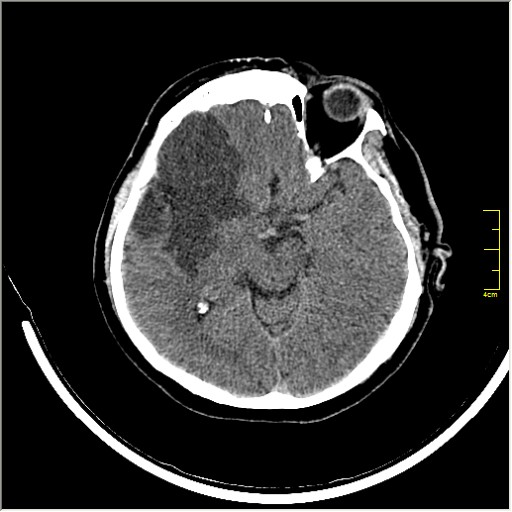

Ну и для полноты картины, привожу контрольные КТ сканы выполненные через 24 часа:

Этот признак называется [Dense MCA sign]; за счёт наличия тромбоза в её просвете. Этот признак является одним из ранних указующих КТ признаков при ишемическом инфаркте головного мозга. Более подробно об этом вы можете прочитать здесь: http://www.radiologyassistant.nl/en/483910a4b6f14.